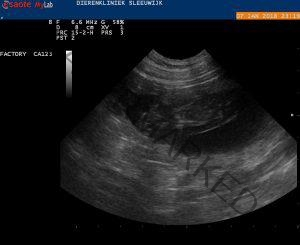

Bij het zien van de echo op het scherm riepen we gelijk “hoera” want Bryn is drachtig!

De dierenarts nam de tijd om een uitgebreide echo te doen en vertelde dat we een groot nest kunnen verwachten! Wat zijn we blij met deze dekking uit de combinatie Bryn x Floris sr.